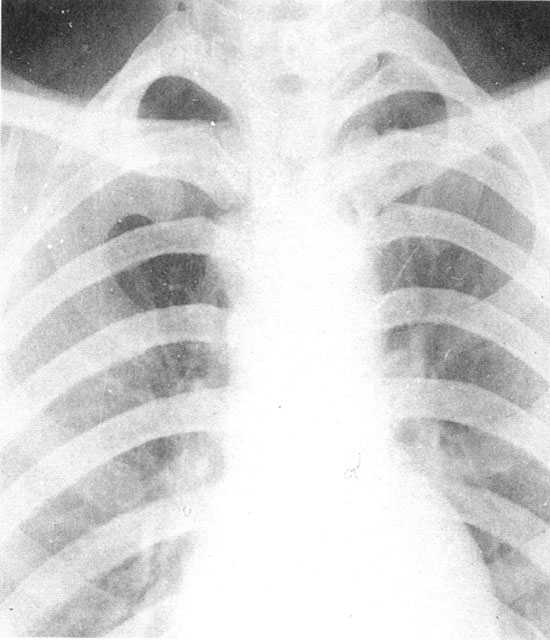

本病进展缓慢,在纵隔形成致密的纤维组织,呈片状或硬块状。好发于前中纵隔的上中部。主要侵犯上腔静脉、无名静脉或奇静脉致发生狭窄或梗阻,其他器官如大的肺血管或食管、气管、支气管亦可受累。少数患者可同时发生颈部纤维化和腹膜后纤维化。